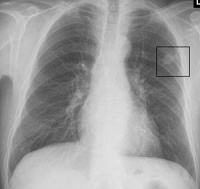

形体明显消瘦,精神萎靡不振,间或烦躁易怒,夜间潮热盗汗,失眠多梦,头晕目花,软弱无力。舌质暗红或绛,舌苔薄少,脉沉细弦涩。本型常系肾上腺结核患者的临床表现,在肾上腺区x线平片上常可发现钙化阴影,可作为本病系结核性的有力佐证。

实验室检查显示,血钠降低,血钾升高,血钠血钾比数小于30。血清氯化物降低,血糖降低。X线摄片,肾上腺可见钙化点。